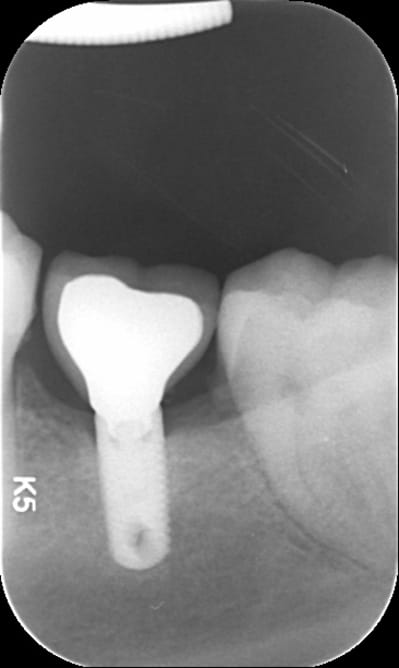

j'ai récupéré une patiente dont le dentiste est parti à la retraite.

Le pilier de la couronne sur 36 est dévissé en partit, et bien qu'il y ait une alvéolyse, l'hygiène est bonne et la gencive saine,

j'aurai bien voulu juste resserrer le pilier.

Savez-vous quel implant c'est et quel tournevis irait ?

Biomet 3i parallel walled?